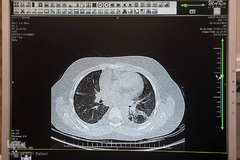

روز جهانی کودک امسال در حالی سپری می‌شود که کودکان در حصار پروتکل‌های بهداشتی کرونا محصور هستند، قواعدی که با دنیای کودکانه، بازی‌ها و جمع‌های نزدیک دوستانه در محل و مدرسه همخوان نیست. اما زورگویی این خرده ویروس برای کودکان بیمار شهر بیشتر است و با کوچک کردن زمین بازیشان به یک تخت، نمکی بر زخم‌های قبلیشان زده است. بیمارستان طبی کودکان یکی از باغچه‌هایی است که میزبان این نوگلان درگیر بیماری است. به انگیزه روز جهانی کودک به دنیای کودکانه آنان در این بیمارستان سری زدیم.